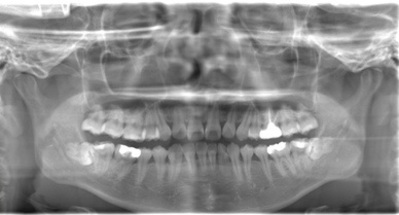

CASE 1

| 年齢・性別 | 30代・女性 |

| 主訴 | 左右に分けて親知らずを抜きたい、できれば痛くなく抜きたい |

| 親知らずのはえ方 | 完全に出ていてまっすぐはえている |

| 抜歯期間 | 15分 |

| 抜歯費用 | 約2,000円(保険内) |

| 抜歯内容 |

何度か虫歯になり痛みはないが早めに抜きたい。 完全に頭が出ているため歯ぐきを切ったり骨を削らずに抜歯しました。 根の形も単純なため抜歯自体は5分もかからず上下ともに終わりました。 術後痛みや腫れも出ていません。 抜歯後は感染をしやすいため必ず抗生物質を飲み切ってください。 |